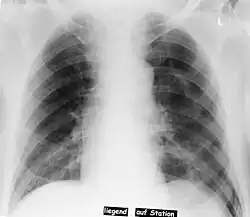

Deep sulcus sign

| Pneumothorax left sided | |

| Differential diagnosis | pneumothorax |

In radiology, the deep sulcus sign on a supine chest radiograph is an indirect indicator of a pneumothorax.[1][2] In a supine film, it appears as a deep, lucent, ipsilateral costophrenic angle[3] within the nondependent portions of the pleural space as opposed to the apex (of the lung) when the patient is upright. The costophrenic angle is abnormally deepened when the pleural air collects laterally, producing the deep sulcus sign.[4]

Patients with chronic obstructive pulmonary disease (COPD) may exhibit deepened lateral costophrenic angles due to hyperinflation of the lungs and cause a false deep sulcus sign.[4]